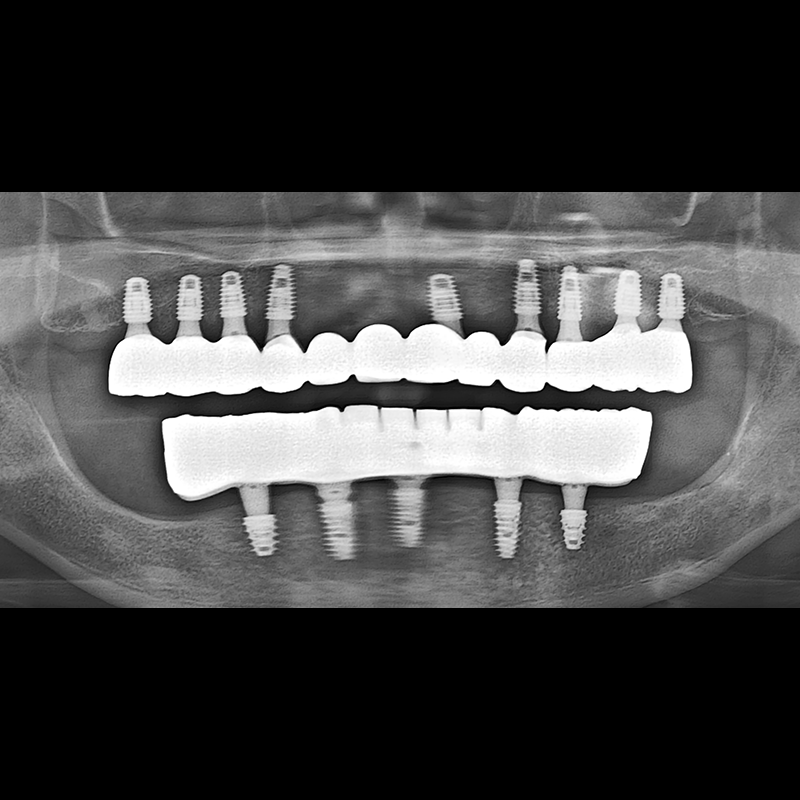

IMPLANT

BEFORE AFTER

种植牙前后的照片 2025.05.30

在缺失的牙齿部分和难以挽救的牙齿位置植入了种植牙。